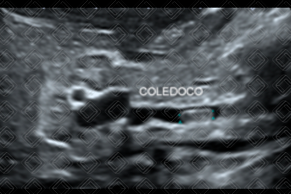

Texto alternativo para a imagem Figura 1. Créditos: Dra. Elazir Mota - Rio de Janeiro/RJ

Descrição das figuras 1 e 2 : Ultrassonografia de abdome. Imagem ecogênica no colédoco distal (setas amarelas).

• Ultrassonografia de abdome: Bom exame para avaliação inicial das vias biliares intra e extra-hepáticas. No entanto, deve ser realizado por radiologista experiente. Na imagem, o cálculo caracteriza-se por imagem ecogênica, podendo haver ou não sombra acústica posterior (figuras 1 e 2);